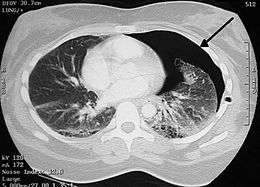

A large right-sided spontaneous pneumothorax (left in the image). An arrow indicates the edge of the collapsed lung | |

Chest X-ray

Traditionally a plain radiograph of the chest, ideally with the X-ray beams being projected from the back (posteroanterior, or "PA"), has been the most appropriate first investigation. These are usually performed during maximal inspiration (holding one's breath); no added information is gathered by obtaining a chest X-ray in expiration (after exhaling).[12][13] If the PA X-ray does not show a pneumothorax but there is a strong suspicion of one, lateral X-rays (with beams projecting from the side) may be performed, but this is not routine practice.[13][17] It is not unusual for the mediastinum (the structure between the lungs that contains the heart, great blood vessels and large airways) to be shifted away from the affected lung due to the pressure differences. This is not equivalent to a tension pneumothorax, which is determined mainly by the constellation of symptoms, hypoxia, and shock.[12]

The size of the pneumothorax (i.e. the volume of air in the pleural space) can be determined with a reasonable degree of accuracy by measuring the distance between the chest wall and the lung. This is relevant to treatment, as smaller pneumothoraces may be managed differently. An air rim of 2 cm means that the pneumothorax occupies about 50% of the hemithorax.[13] British professional guidelines have traditionally stated that the measurement should be performed at the level of the hilum (where blood vessels and airways enter the lung) with 2 cm as the cutoff,[13] while American guidelines state that the measurement should be done at the apex (top) of the lung with 3 cm differentiating between a "small" and a "large" pneumothorax.[23] The latter method may overestimate the size of a pneumothorax if it is located mainly at the apex, which is a common occurrence.[13] The various methods correlate poorly, but are the best easily available ways of estimating pneumothorax size.[13][17] CT scanning (see below) can provide a more accurate determination of the size of the pneumothorax, but its routine use in this setting is not recommended.[23]

Not all pneumothoraces are uniform; some only form a pocket of air in a particular place in the chest.[13] Small amounts of fluid may be noted on the chest X-ray (hydropneumothorax); this may be blood (hemopneumothorax).[12] In some cases, the only significant abnormality may be the "deep sulcus sign", in which the normally small space between the chest wall and the diaphragm appears enlarged due to the abnormal presence of fluid.[14]